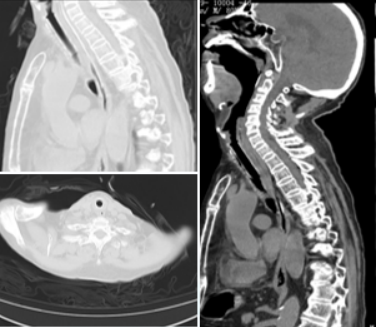

1月12日复查CT:支架位置良好(图13)。予无创通气与高流量交替,拟T管置入。1月14日患者夜间出现刺激性咳嗽,1月15日复查气管镜(软镜)示:声门下腔水肿并坏死物致管腔中度狭窄(图14),冷冻清理坏死物后见硅酮支架下移10 mm,支架第二次移位;声门及声门下腔注入地塞米松5 mg。硅酮支架难题就是肉芽增生和移位,与家属充分沟通后同意T管置入。1月17日全麻硬镜:声门下腔及气管起始部黏膜水肿并坏死物致管腔轻度狭窄,取出硅酮支架,置入T管(图15)。1月19日和20日两次复查气管镜:T管在位,管腔上缘少许坏死物(图16)。病例4:85岁,女性,反复气促2年,外院住院考虑气管外压性狭窄,支架置入失败,心跳骤停,困难插管后3月7日转入我科。入科:气管插管,HR 96次/min,BP 107/86 mmHg,R 24次/min,SpO2 98%(FiO2 100%)。腹膨隆明显。急查胸腹CT示腹腔、纵隔、胸壁及颈部多发积气(图17)。予腹腔穿刺排气。3月11日复查CT示积气明显减少(图18)。3月12日行全院大会诊,考虑结节性甲状腺肿可能,可考虑外科手术。下一步治疗面临难题:继续插管?还是支架置入后手术?与家属充分沟通后,家属拒绝再次支架置入,故继续插管并于3月15日于耳鼻喉科行甲状腺全切术+气管悬吊重建术。术后第3天(3月18日)拔除气管导管,3月28日顺利出院(图19)。因此,并非所有良性气道狭窄都需要介入治疗,解除原发病因最重要。

图19 3月7日和3月28日胸部CT对比